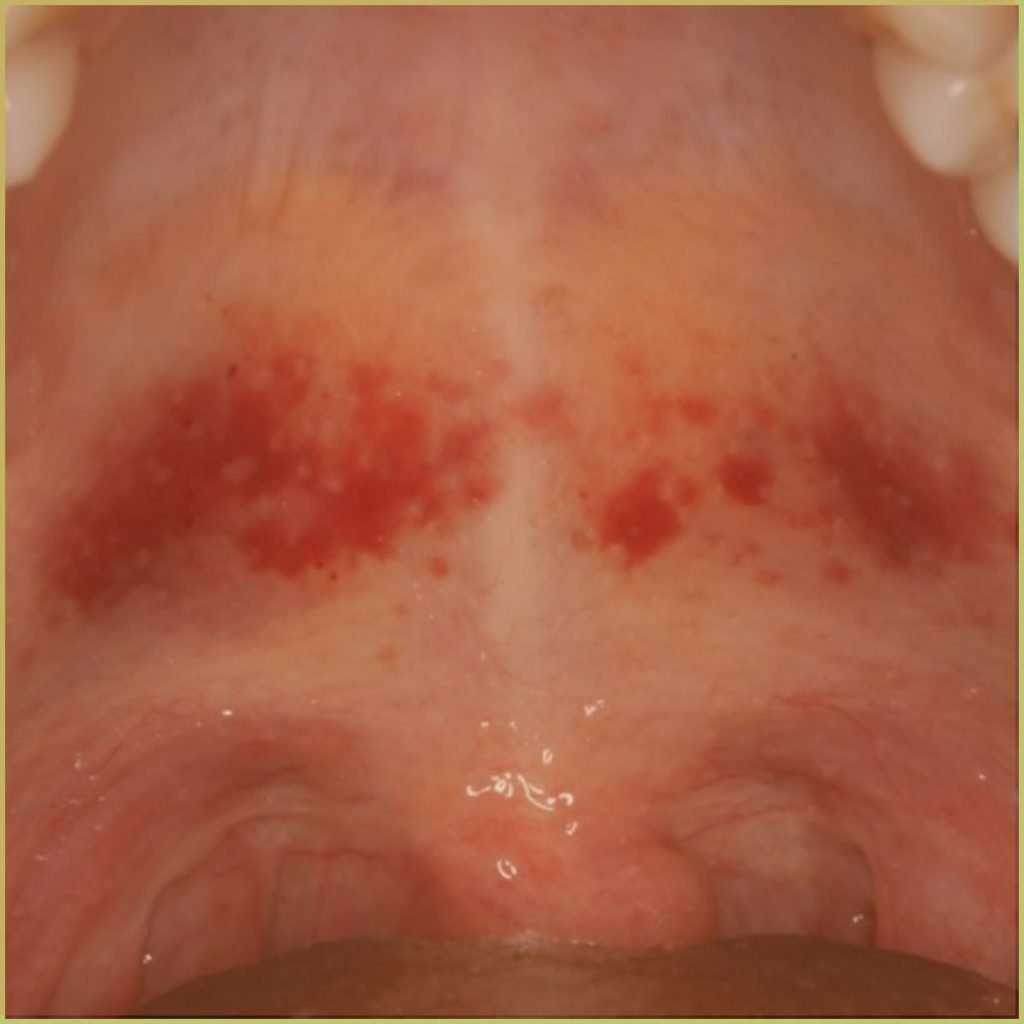

PLASMA CELL GINGIVITIS

Plasma Cell Gingivitis is a rare benign condition characterized by well demarcated erythematous and edematous gingivitis. It is usually caused by a hypersensitivity to an agent such as cinnamon, additive flavors, toothpaste, mouthwash or plaque antigens. The common clinical presentation includes:

- Erythema and edema with a velvety gingival surface.

- Surface epithelium becomes non-keratinized.

- Limited to the attached gingiva and often extends to the mucogingival junction.

Diagnosis is based on the lesion history, clinical presentation and microscopic findings, which may include:

- Dense infiltrate of normal plasma cells into the subepithelial gingival tissue.

- Plasma cells are separated into aggregates by strands of collagen.

Your differential diagnosis should include:

- Lupus erythematosus.

- Wegener’s granulomatosis.

- Chronic candidiasis.

- Lichen planus or lichenoid reaction.

- Mucous membrane pemphigoid.

Treatment usually involves the removal of the etiological agent only.